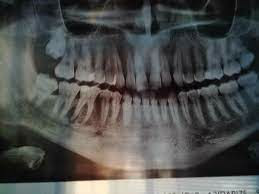

تشخيص خراج الأسنان :

يتم التشخيص عادةً من خلال الفحص السريري ، وفحص الأشعة السينية لتحديد موقع الخراج وامتداده ، وقد يطلب الطبيب فحوصات إضافية إذا كان هناك اشتباه بانتشار العدوى . في بعض الأحيان ، يُستخدم التصوير المقطعي المحوسب (CT) لتقييم مدى انتشار الالتهاب بدقة أكبر .